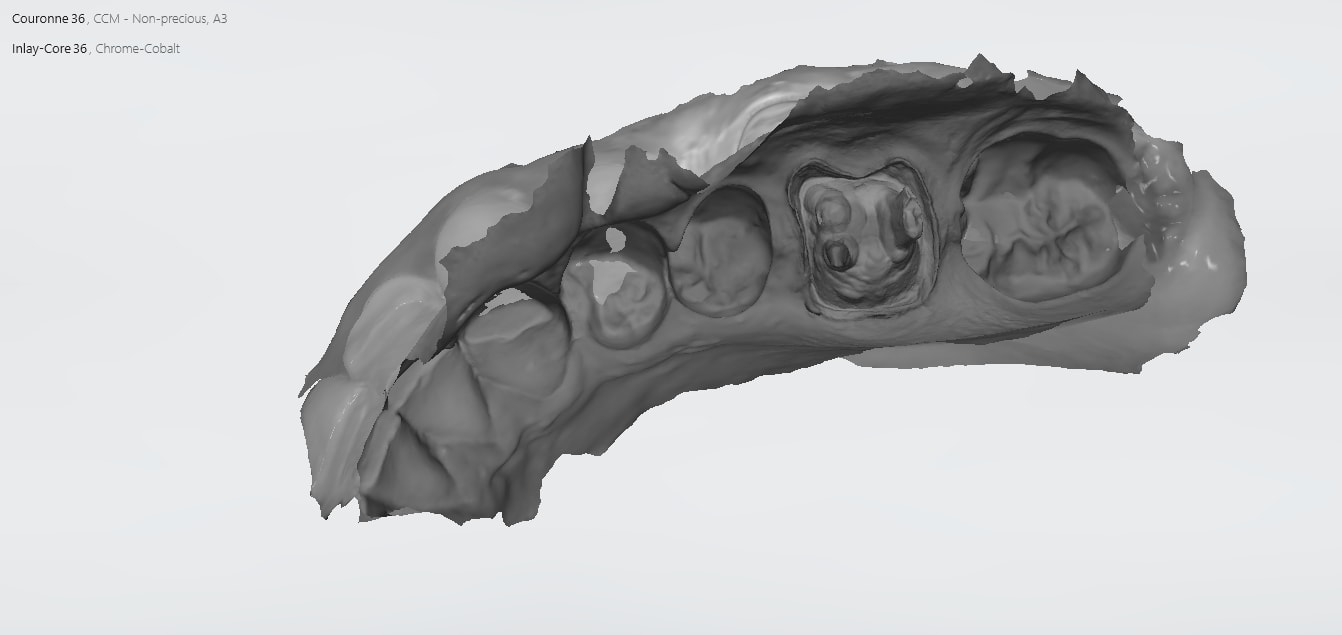

IC ceram 23 + stellite.

Idem que Chicot: Oneshot mais avec un peu plus d’éléments : 3IC, 8 CCM, 1 Stelitte. Aucune retouche autre qu’occlusale. Même Labo, c’est basique mais efficace

Pas mal. Attachements + augmentation de DV en plus.